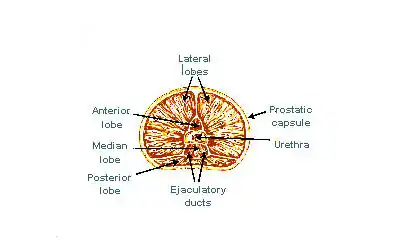

The internal structure of the prostate has been described using both lobes and zones.[4][1] Because of the variation in descriptions and definitions of lobes, the zone classification is used more predominantly.[1]

The "lobe" classification describes lobes that, whilst originally defined in the foetus, are also visible in gross anatomy, including dissection and when viewed endoscopically.[4][3] The five lobes are the anterior lobe or isthmus; the posterior lobe; the right and left lateral lobes, and the middle or median lobe.